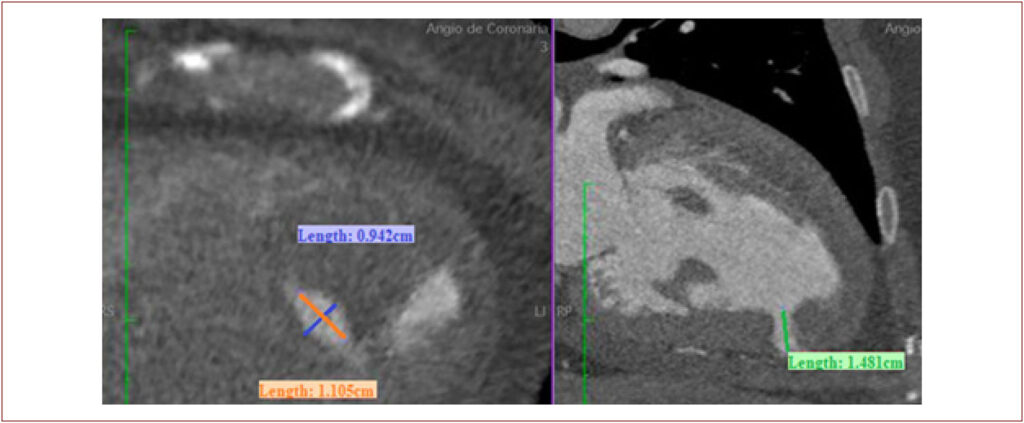

Left ventricular pseudoaneurysm (LVPSA) is a rare complication after myocardial infarction (MI) with a significant risk of rupture if untreated. Given the elevated surgical risk in this context, alternative treatments are emerging. This case describes a percutaneous closure of an LVPSA after extensive MI with delayed revascularization.